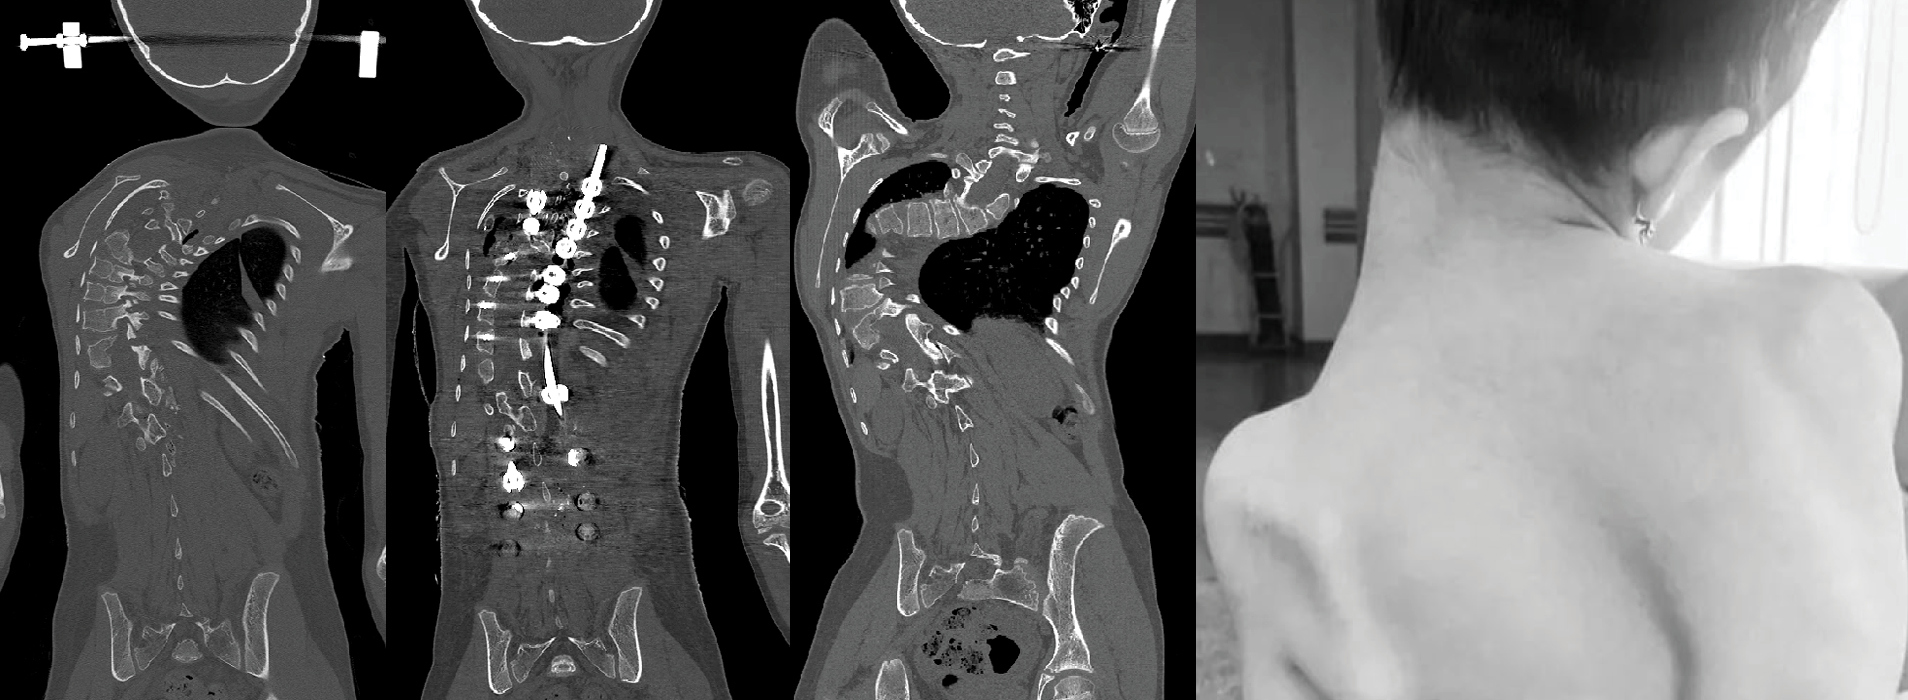

A 12-year-old girl from Kyrgyzstan came to Aakash Healthcare, New Delhi because she suffered from a rare condition that affects approximately three children in every one hundred thousand called Progressive Scoliosis Dorsolumbar. Dorsal scoliosis affects the portion of the spine between the bottom of the neck and the top of the pelvis and causes a severe curvature. In her case, a 130 degree curve, in addition to pelvic misalignment caused by different-sized hips, was causing severe pain that left her unable to walk and was only getting worse.

The 12-year-old patient underwent a 16-hour spine surgery in two phases by the Ortho-Spine division at Aakash Healthcare. Custom-made 3D printed jigs played an important role in pre-operative planning, giving the surgeons an opportunity to practice the complicated screw insertion procedure on a 3D printed model which was a traced copy of the deformed spine. In the first stage of surgery, which lasted six hours, soft tissue adhesions were removed, and multiple osteotomies, or bone cuts, were used to increase the spine’s flexibility while correcting the alignment in the coronal plane. The second phase of the surgery involved the insertion of several titanium screws. The positioning of the screw, its size, length, and direction was performed with the help of biocompatible 3D printed jigs.

Due to the spine’s severe deformity and the difficulty in inserting screws, the 3D printed jigs served as a crucial component to execute the surgery safely and without complications. The 3D print aided in surgical planning by calculating the size of the bone pedicles through which screws were put.

Dr. Chandra added, “At every stage, 3D printing helped to plan the screw’s size, length, and direction. The most important feature is that it considerably lowered the risk of neurological complications and the associated problems. We could achieve almost 70 percent to 80 percent correction after surgery. Now her spine curvature has been reduced to just 30 degrees.”